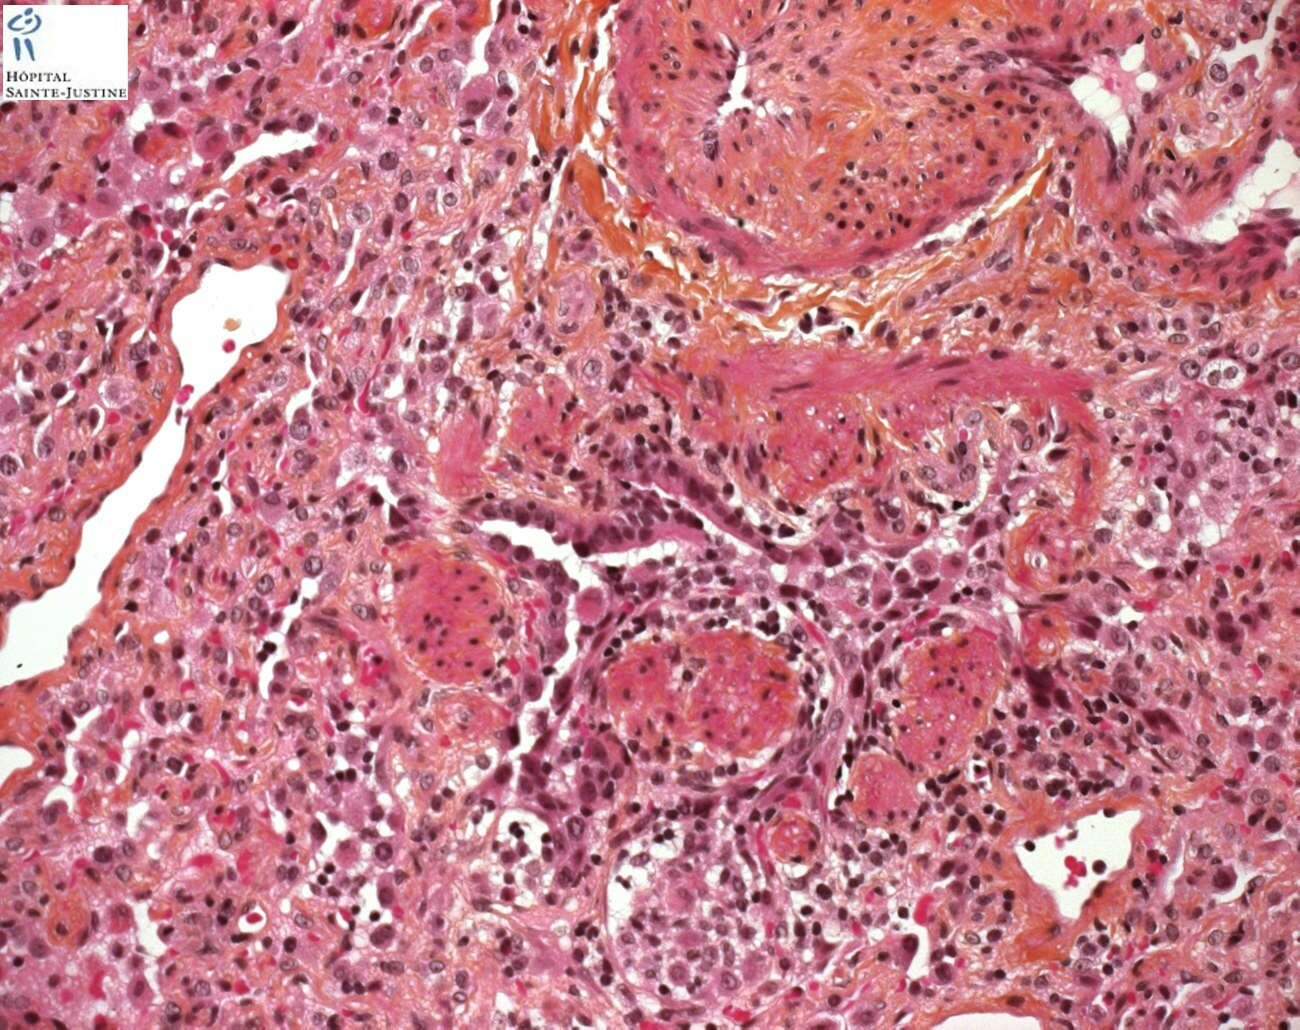

necrotizing bronchiolitis